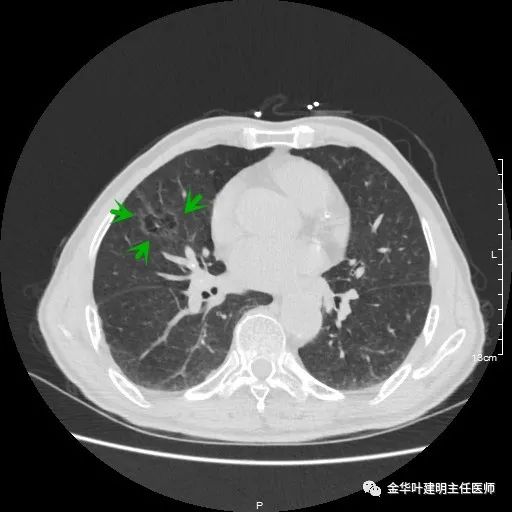

以上示左上叶病灶2。病灶虽然似慢性炎,但有收缩力,有毛刺征,在右侧诸多病灶考虑多原发肺癌的前提下,此灶是恶性的可能性非常大,不能单纯认为其是慢性炎性病灶。就此单灶来看,可以局部切除病检,若示浸润性腺癌,则有肺叶切除的指征。